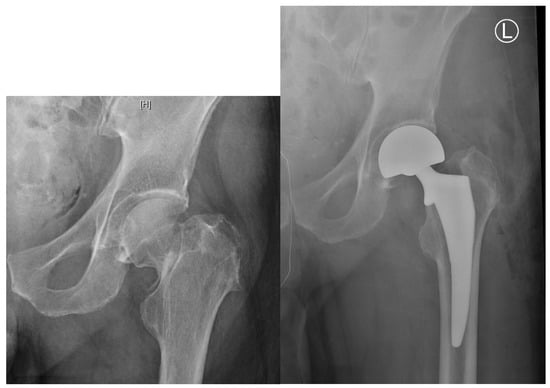

2.4. Displaced Femoral Neck Fractures: Hemiarthroplasty vs. Total Hip Arthroplasty